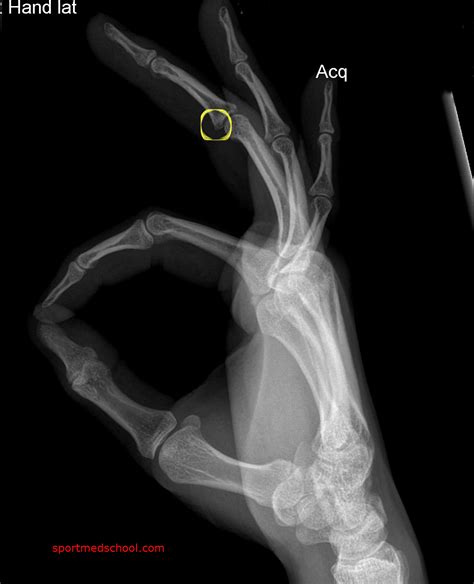

If you suspect a broken finger, it is essential to seek medical attention promptly. A healthcare professional will perform a physical examination and may order X-rays to confirm the diagnosis. Treatment options for a broken finger typically include:

In some cases, surgery may be required to realign the bones or repair damaged tendons or ligaments. Physical therapy may also be recommended to restore range of motion and strength in the finger.